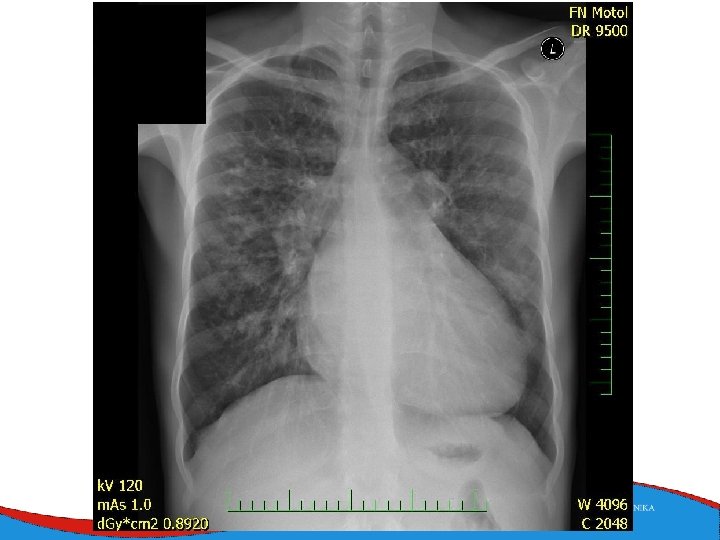

Signs, symptoms and diagnostics • Heart failure- low CO, congestion • Arrhythmias • Sudden death • SVT, AF- mitral regurgitation- atrial dilatation • Thrombi in left ventricle/ left atrial appendage – CMP • ECG • ECHO – ventricular dilatation and dysfunction • Lab – NT-pro. BNP • Selective coronarography- CAD exclusion • Stress test- prognosis • MRI • EMB– inflammatory CMP

Therapy Sudden death prevention Based on symptoms and severe systolic dysfunction (EF less than 35% + symtomatologie NYHA II-IV) Heart failure therapy Drug therapy CRT Mechanical assist devices Heart transplant Prevention of thromboembolic complications of atrial fibrillation - NOAC, Warfarin